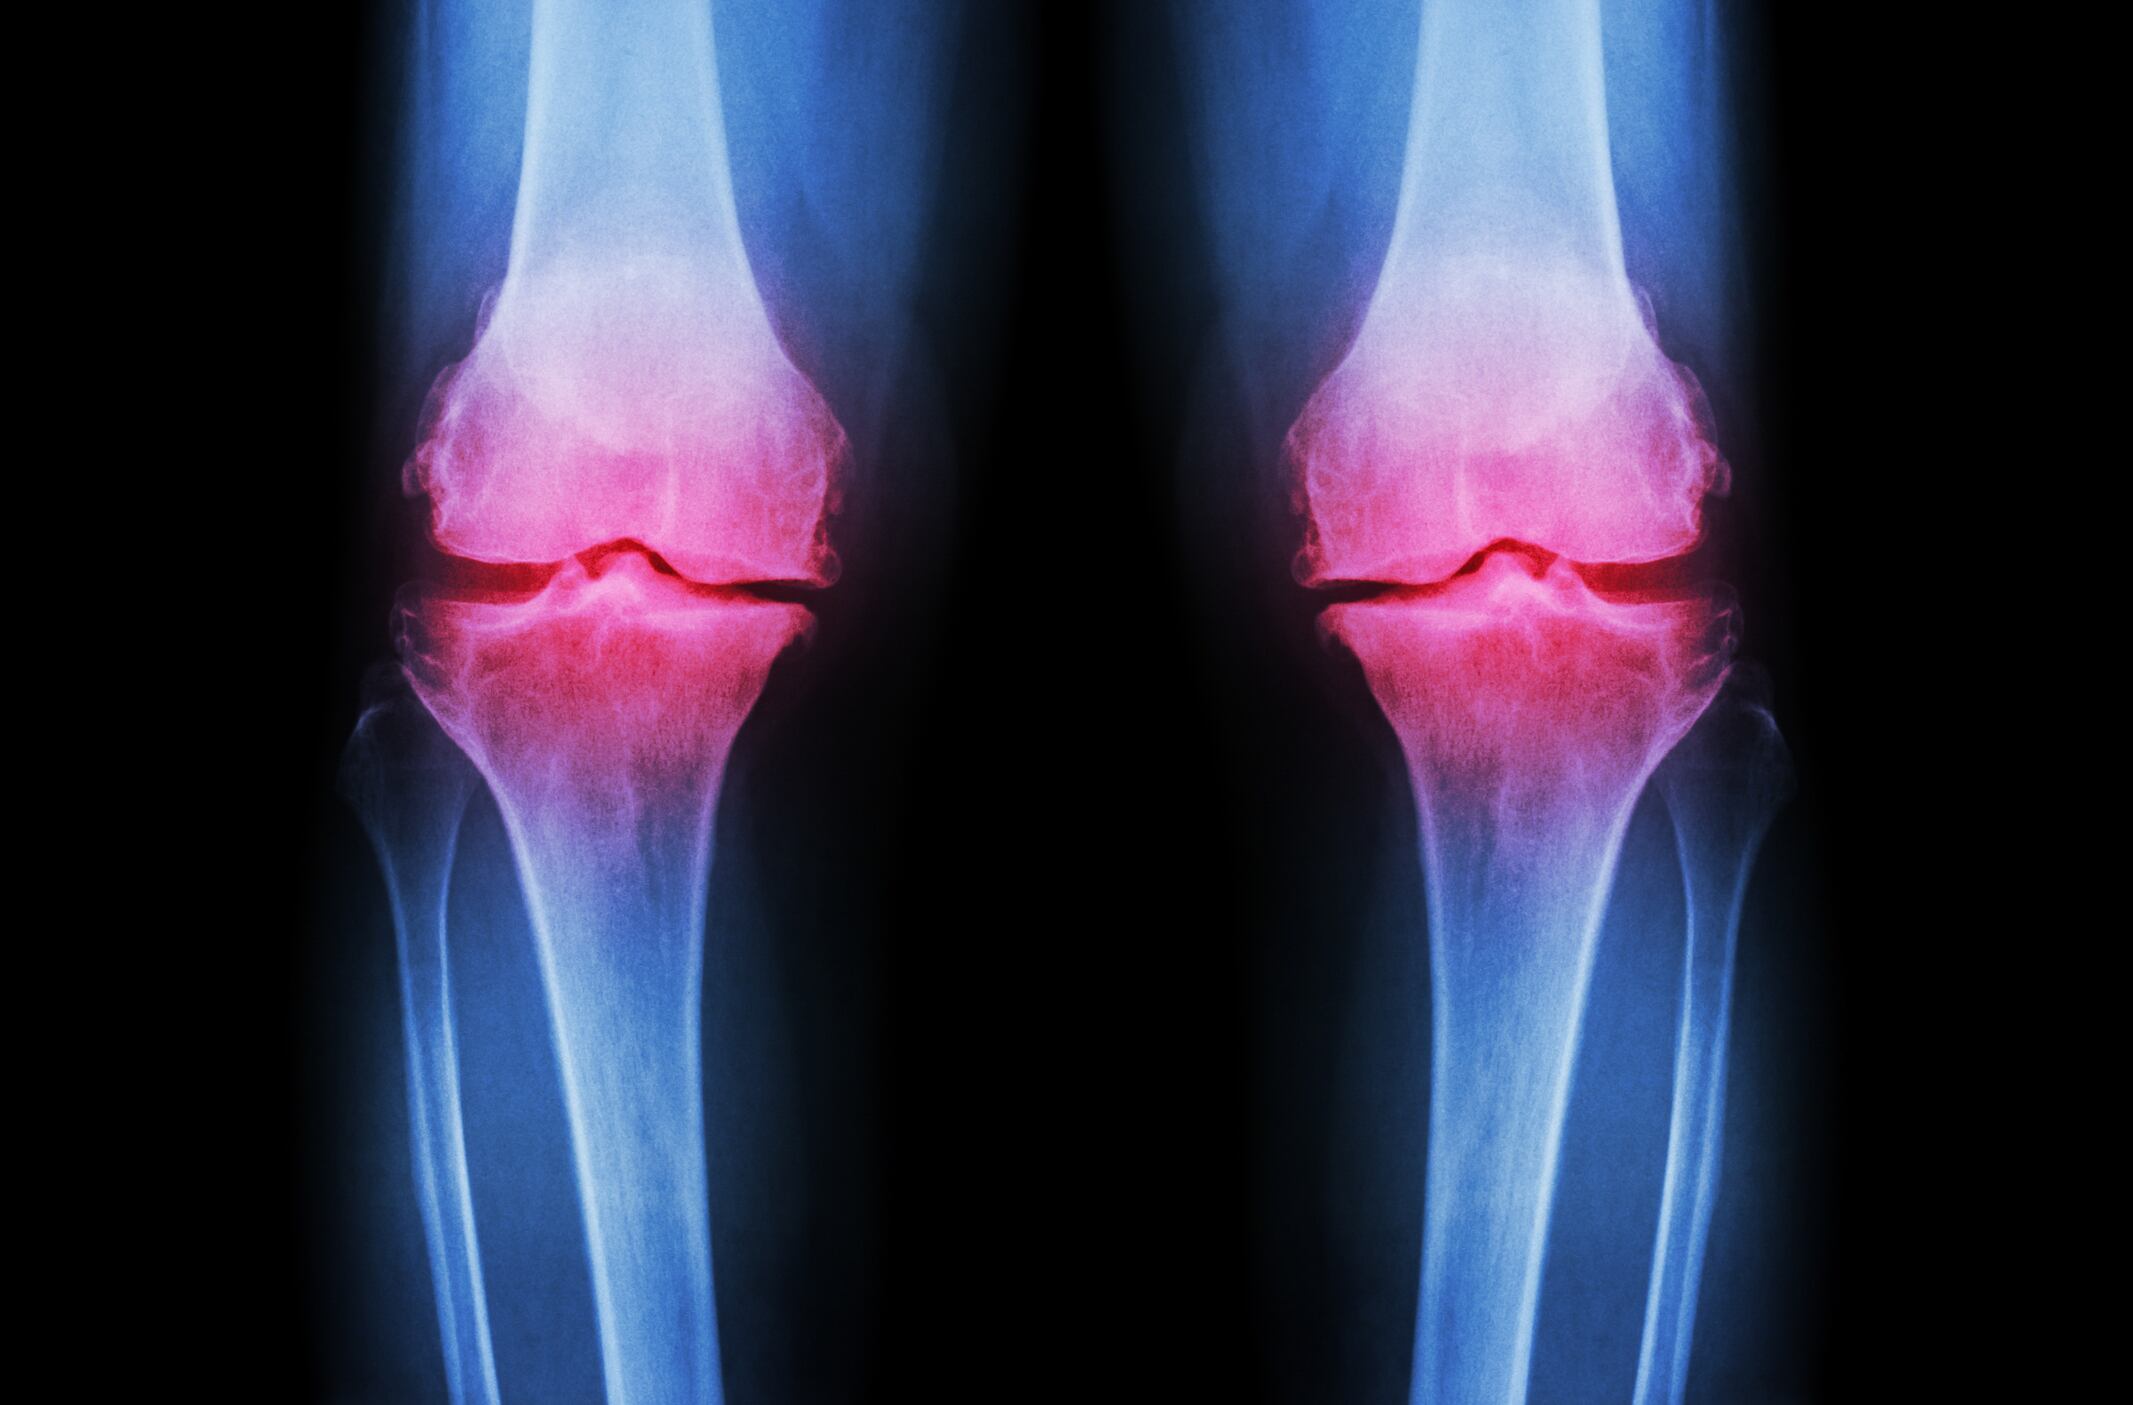

Italian scientists report in The Journal of Alternative and Complementary Medicine that the combination significantly improved knee, hip, and generalized OA.

The small study adds to a body of science supporting the potential joint health benefits of Boswellia serrata. The herb grows in dry mountainous regions of India, Northern Africa and Middle East. The oleo gum-resin contains four boswellic acids, one of which, acetyl-11-keto-β-boswellic acid is a potent inhibitor of 5-lipoxygenase, an enzyme responsible for inflammation.